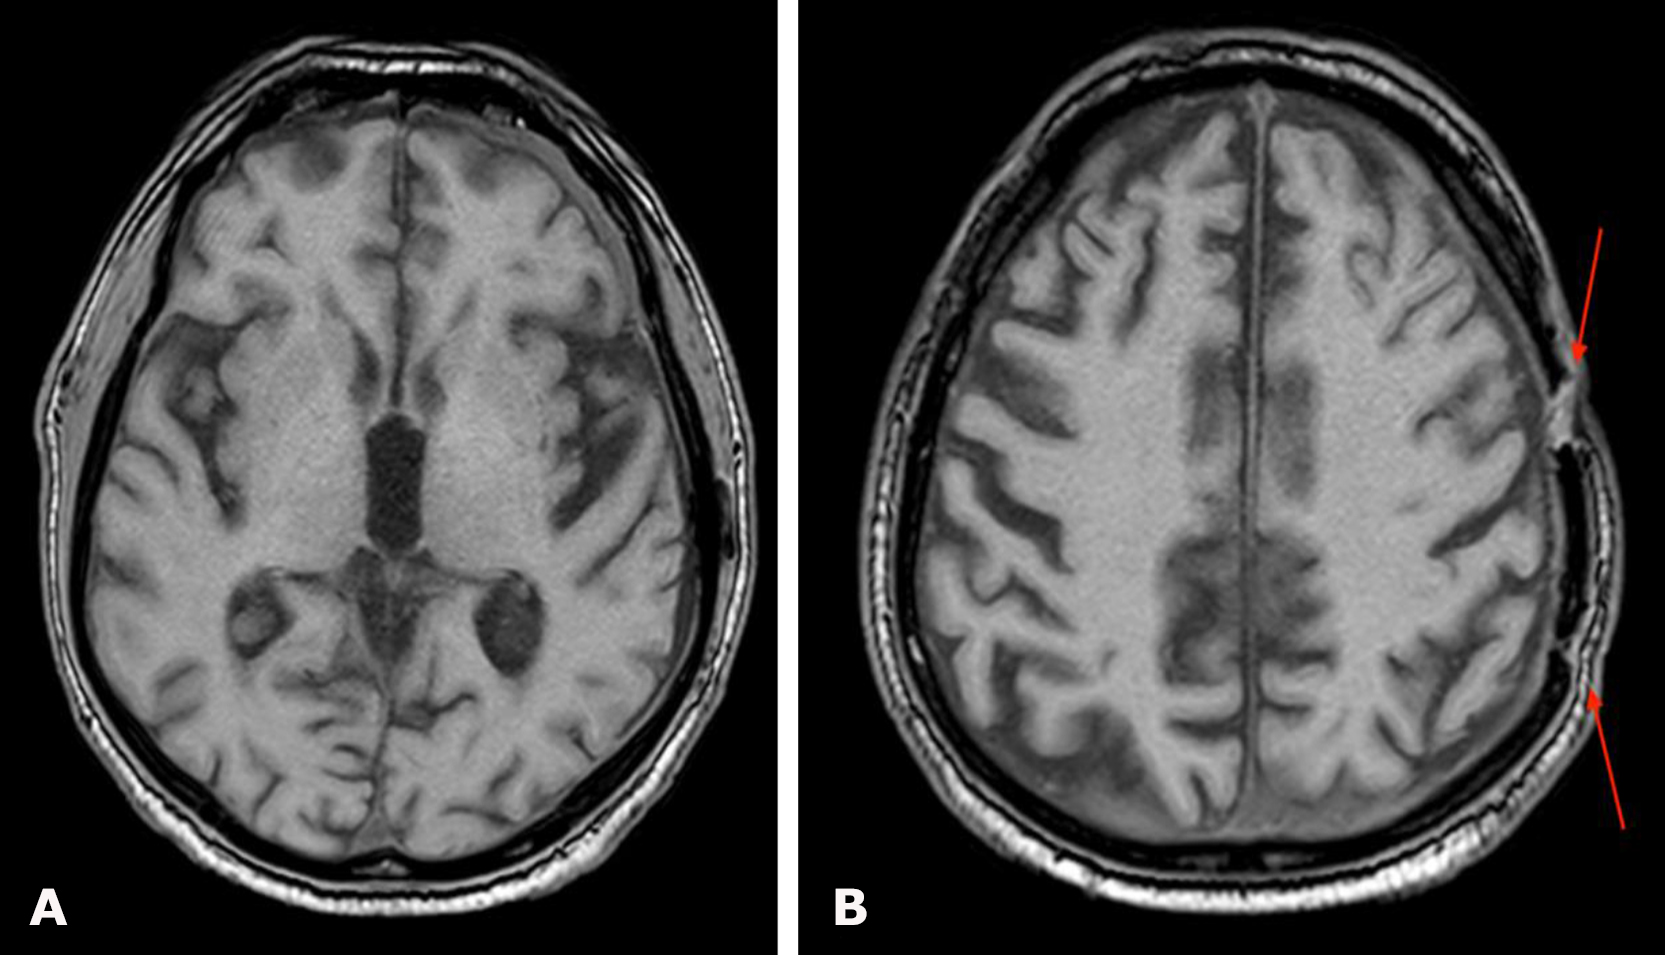

Non-contrast brain CT demonstrated a left-sided hemispheric multiloculated cSDH with dimensions (thickness/length/height) of 17/145/104 mm and an 8-mm midline shift to the right (Fig. 13).

Fig. 13. Preoperative brain CT: A, B – axial projections demonstrating a left-sided hemispheric multiloculated cSDH with marked compression and edema of the left cerebral hemisphere

Given the CT findings and the severity of the patient’s condition, emergency surgery was performed for life-saving indications: osteoplastic craniotomy in the left parietal region, evacuation of the left-sided multiloculated cSDH, and inflow–outflow drainage of the left subdural space on June 11, 2024 (Fig. 14).

Fig. 14. Control brain CT on postoperative day 1: A, B – axial projections. The yellow arrow indicates radiopaque drains of the inflow–outflow drainage system

Given the stability of the patient’s condition, follow-up brain MRI was performed 6 months after surgery (Fig. 16). Complete resolution of the left-sided cSDH was demonstrated, indicating the absence of recurrence, along with restoration of the normal position of the midline brain structures. At follow-up examination, the patient was in satisfactory condition without focal neurological deficits.

Fig. 16. Postoperative brain MRI, T1-weighted images: A, B – axial projections demonstrating the absence of left-sided cSDH. The red arrow indicates residual changes from the previous craniotomy